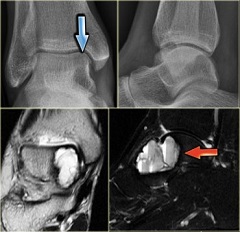

Киста голеностопного сустава

Голеностопный сустав представляет собой сочленение стопы и костей голени (таранной, малоберцовой и большеберцовой костей). Киста голеностопного сустава отличается меньшими размерами, формирование ее также протекает бессимптомно, локализуется на тыльной стороне сустава. Киста голеностопного сустава также является следствием дегенеративных процессов сустава, травм.